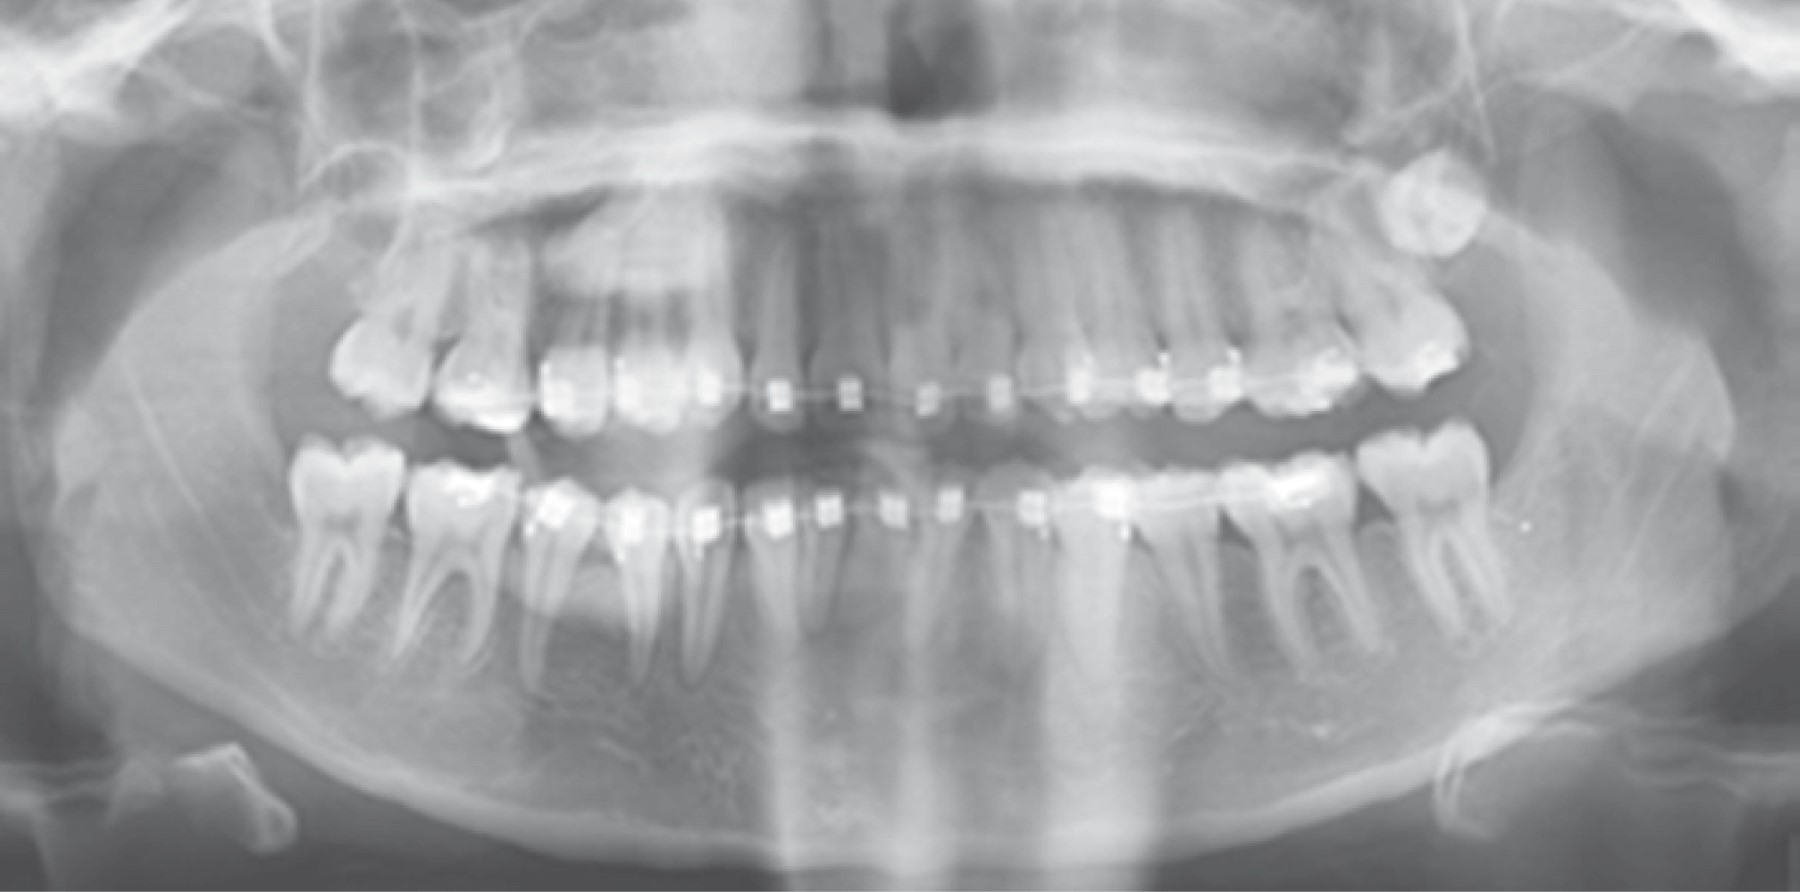

Tal como se refleja en el estudio realizado por Masui M y colaboradores denominado Displacement of lower third molar into floor of mouth: a single institutional experience,8 en el cual desarrollaron un análisis retrospectivo del manejo del tercer molar inferior desplazado hacia el piso de la boca, tomando en cuenta siete pacientes cuyo rango de edades iba de los 20-62 años, entre un periodo de tiempo que abarca del 2010-2020, el cual obtuvo como resultado: seis casos en donde el tercer molar fue desplazado hacia el espacio submandibular y un caso al espacio sublingual. Estas unidades dentarias o fragmentos dentarios, fueron retirados de piso de boca a través de un abordaje intraoral en seis casos, ya que únicamente un caso no se abordó; cuatro casos fueron abordados bajo anestesia general y dos casos bajo anestesia local, al igual que como expresan Tilaveridis I y asociados en el estudio denominado Displacement of maxillary third molar into the infratemporal fossa. A case report9 en donde se reportó el caso de un paciente masculino de 17 años de edad con desplazamiento de tercer molar superior izquierdo, luego de la evaluación de la tomografía computarizada se pudo evidenciar la presencia del tercer molar desplazado en la fosa infratemporal ipsilateral (Figura 1), su intervención fue bajo anestesia general, a través de un abordaje intraoral, en el cual la recuperación de la unidad fue de manera exitosa (Figura 2). De igual manera, Rivas y colegas en su estudio Tercer molar desplazado a fosa pterigomaxilar: reporte de caso5 presentan el caso de un paciente de sexo femenino de 16 años de edad, durante la cirugía de los terceros molares, la unidad 28 fue perdida de vista por parte del operador, indicaron radiografías panorámicas y tomografía de haz helicoidal, después de su evaluación se evidenció la ubicación de la unidad, el cual se encontró en la fosa pterigomaxilar (Figuras 3 y 4). Se realizó un abordaje intraoral bajo anestesia local, hasta alcanzar la unidad dentaria desplazada y recuperarla de manera exitosa.

Figura 1

Figura 2